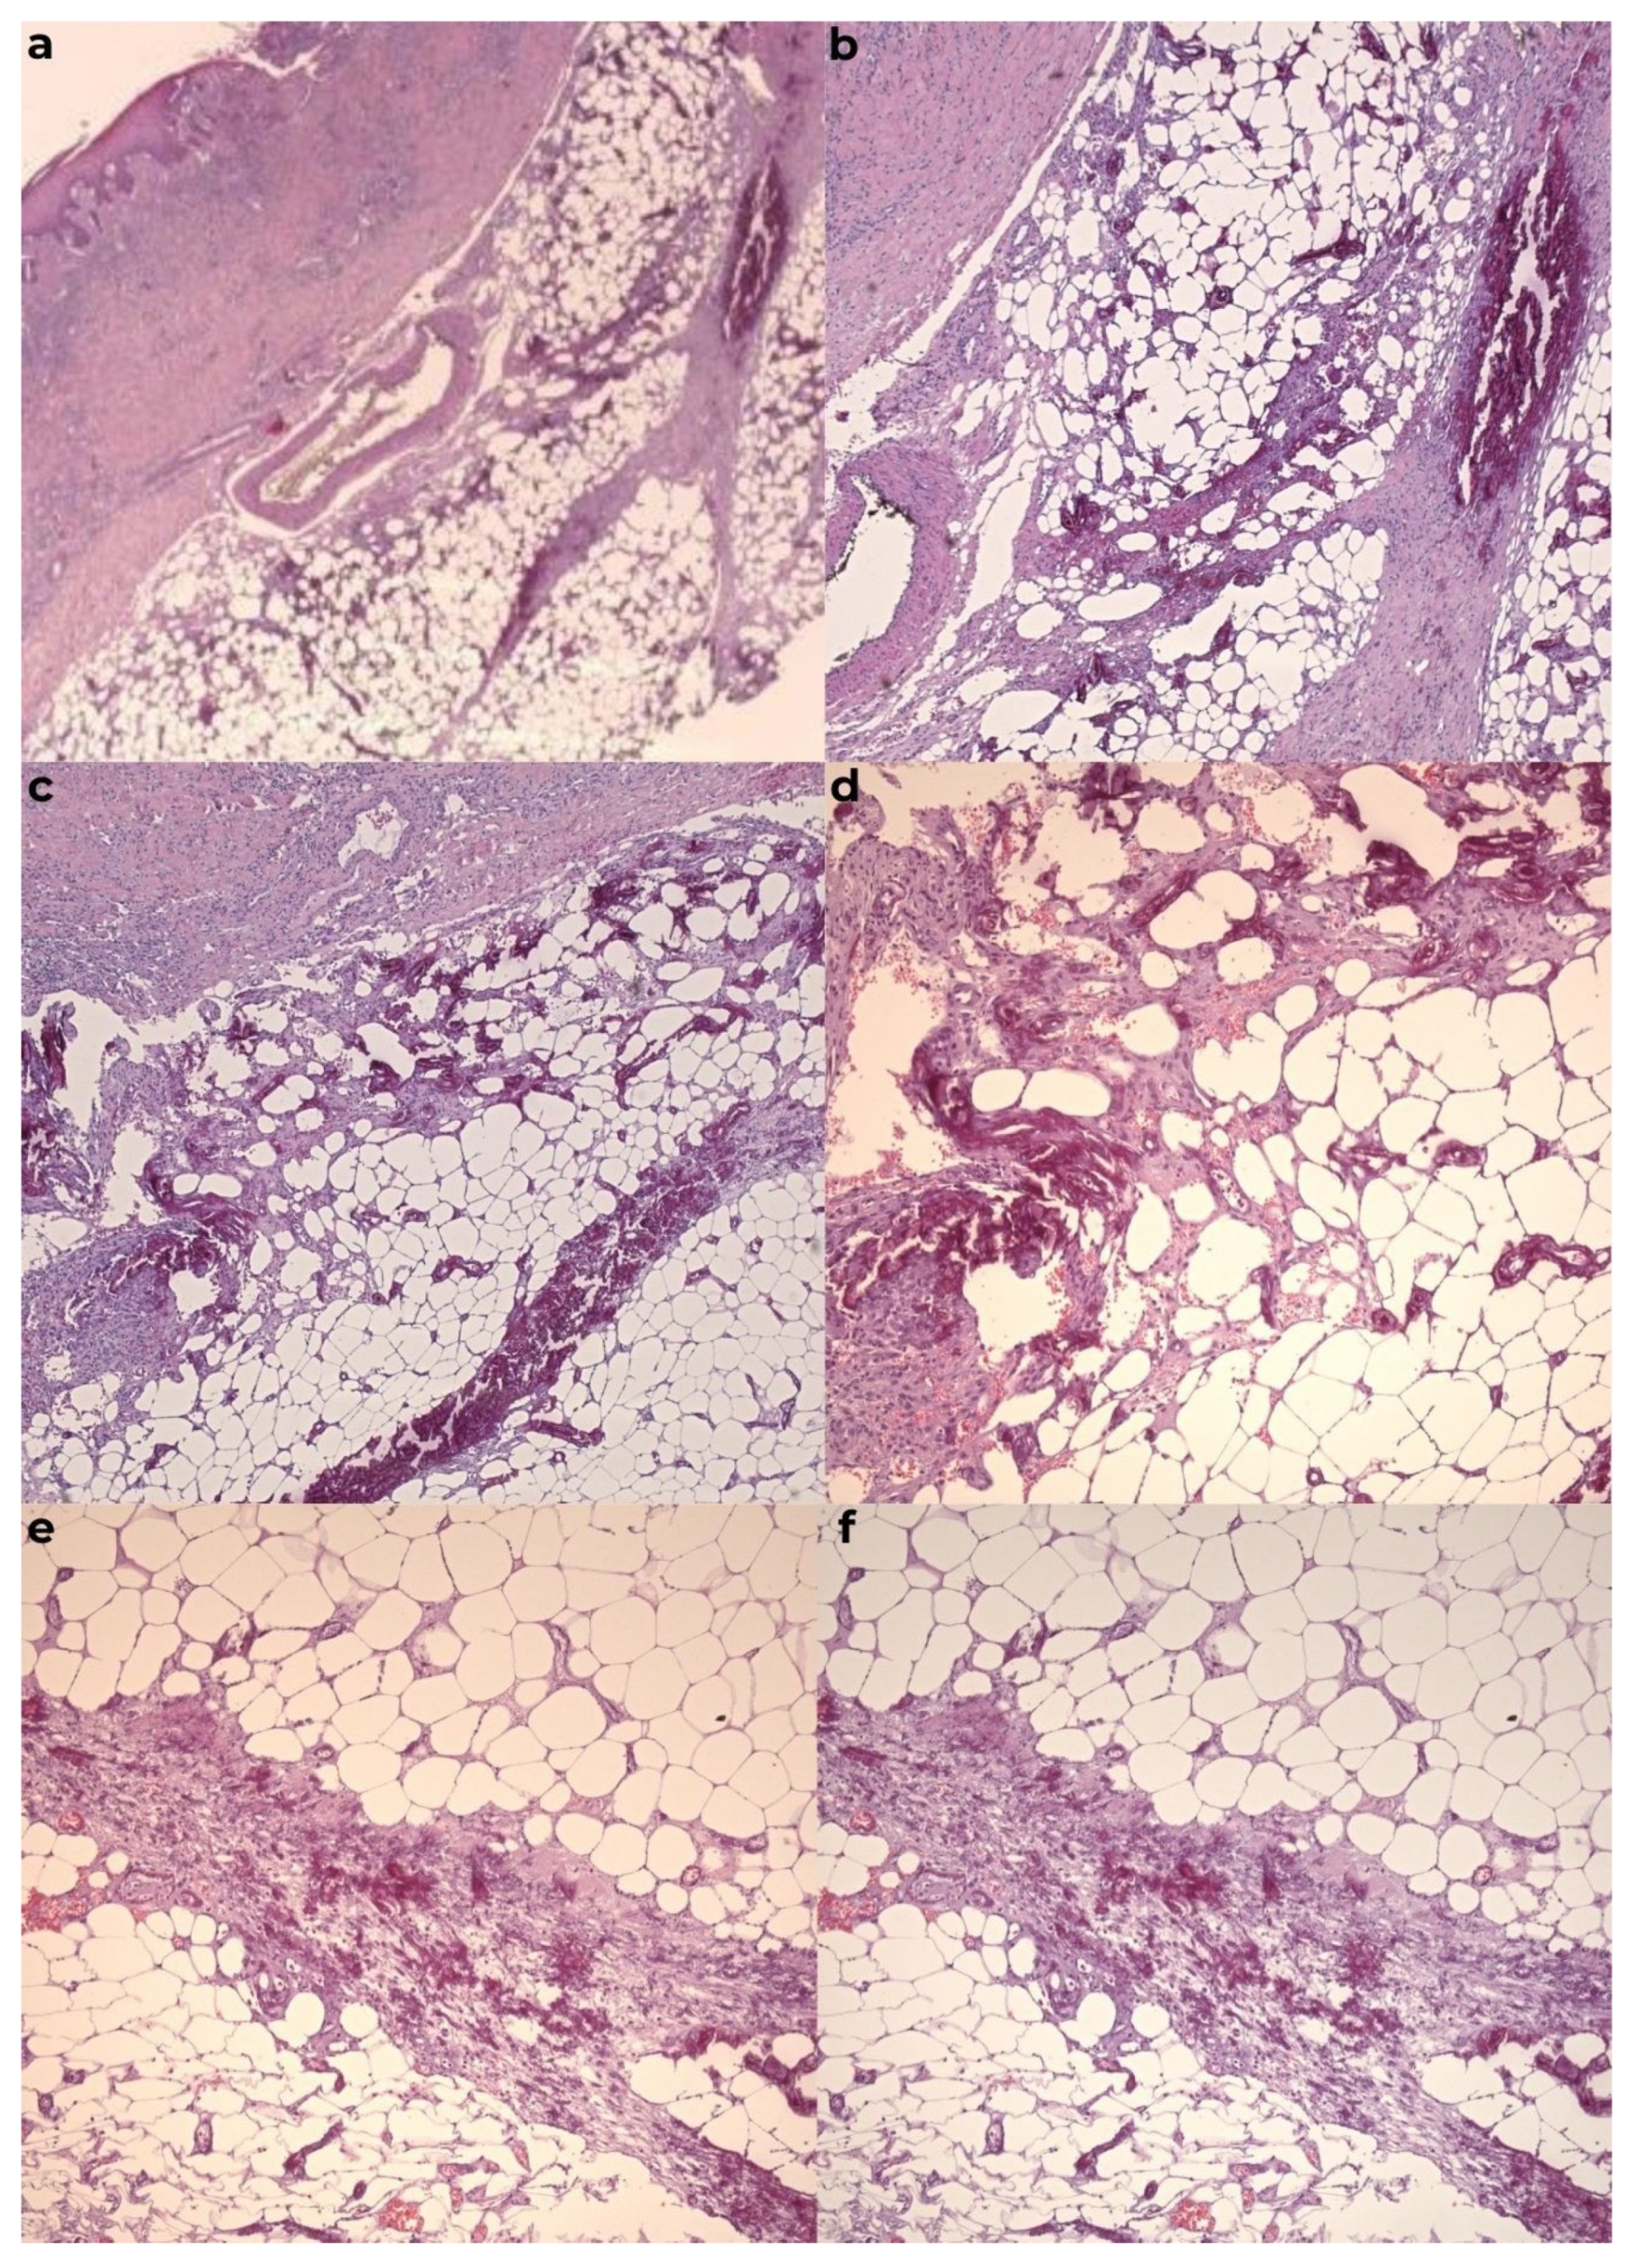

2. Case Presentation

2.1. Case Series

2.1.1. Case Report 1

2.1.2. Case Report 2